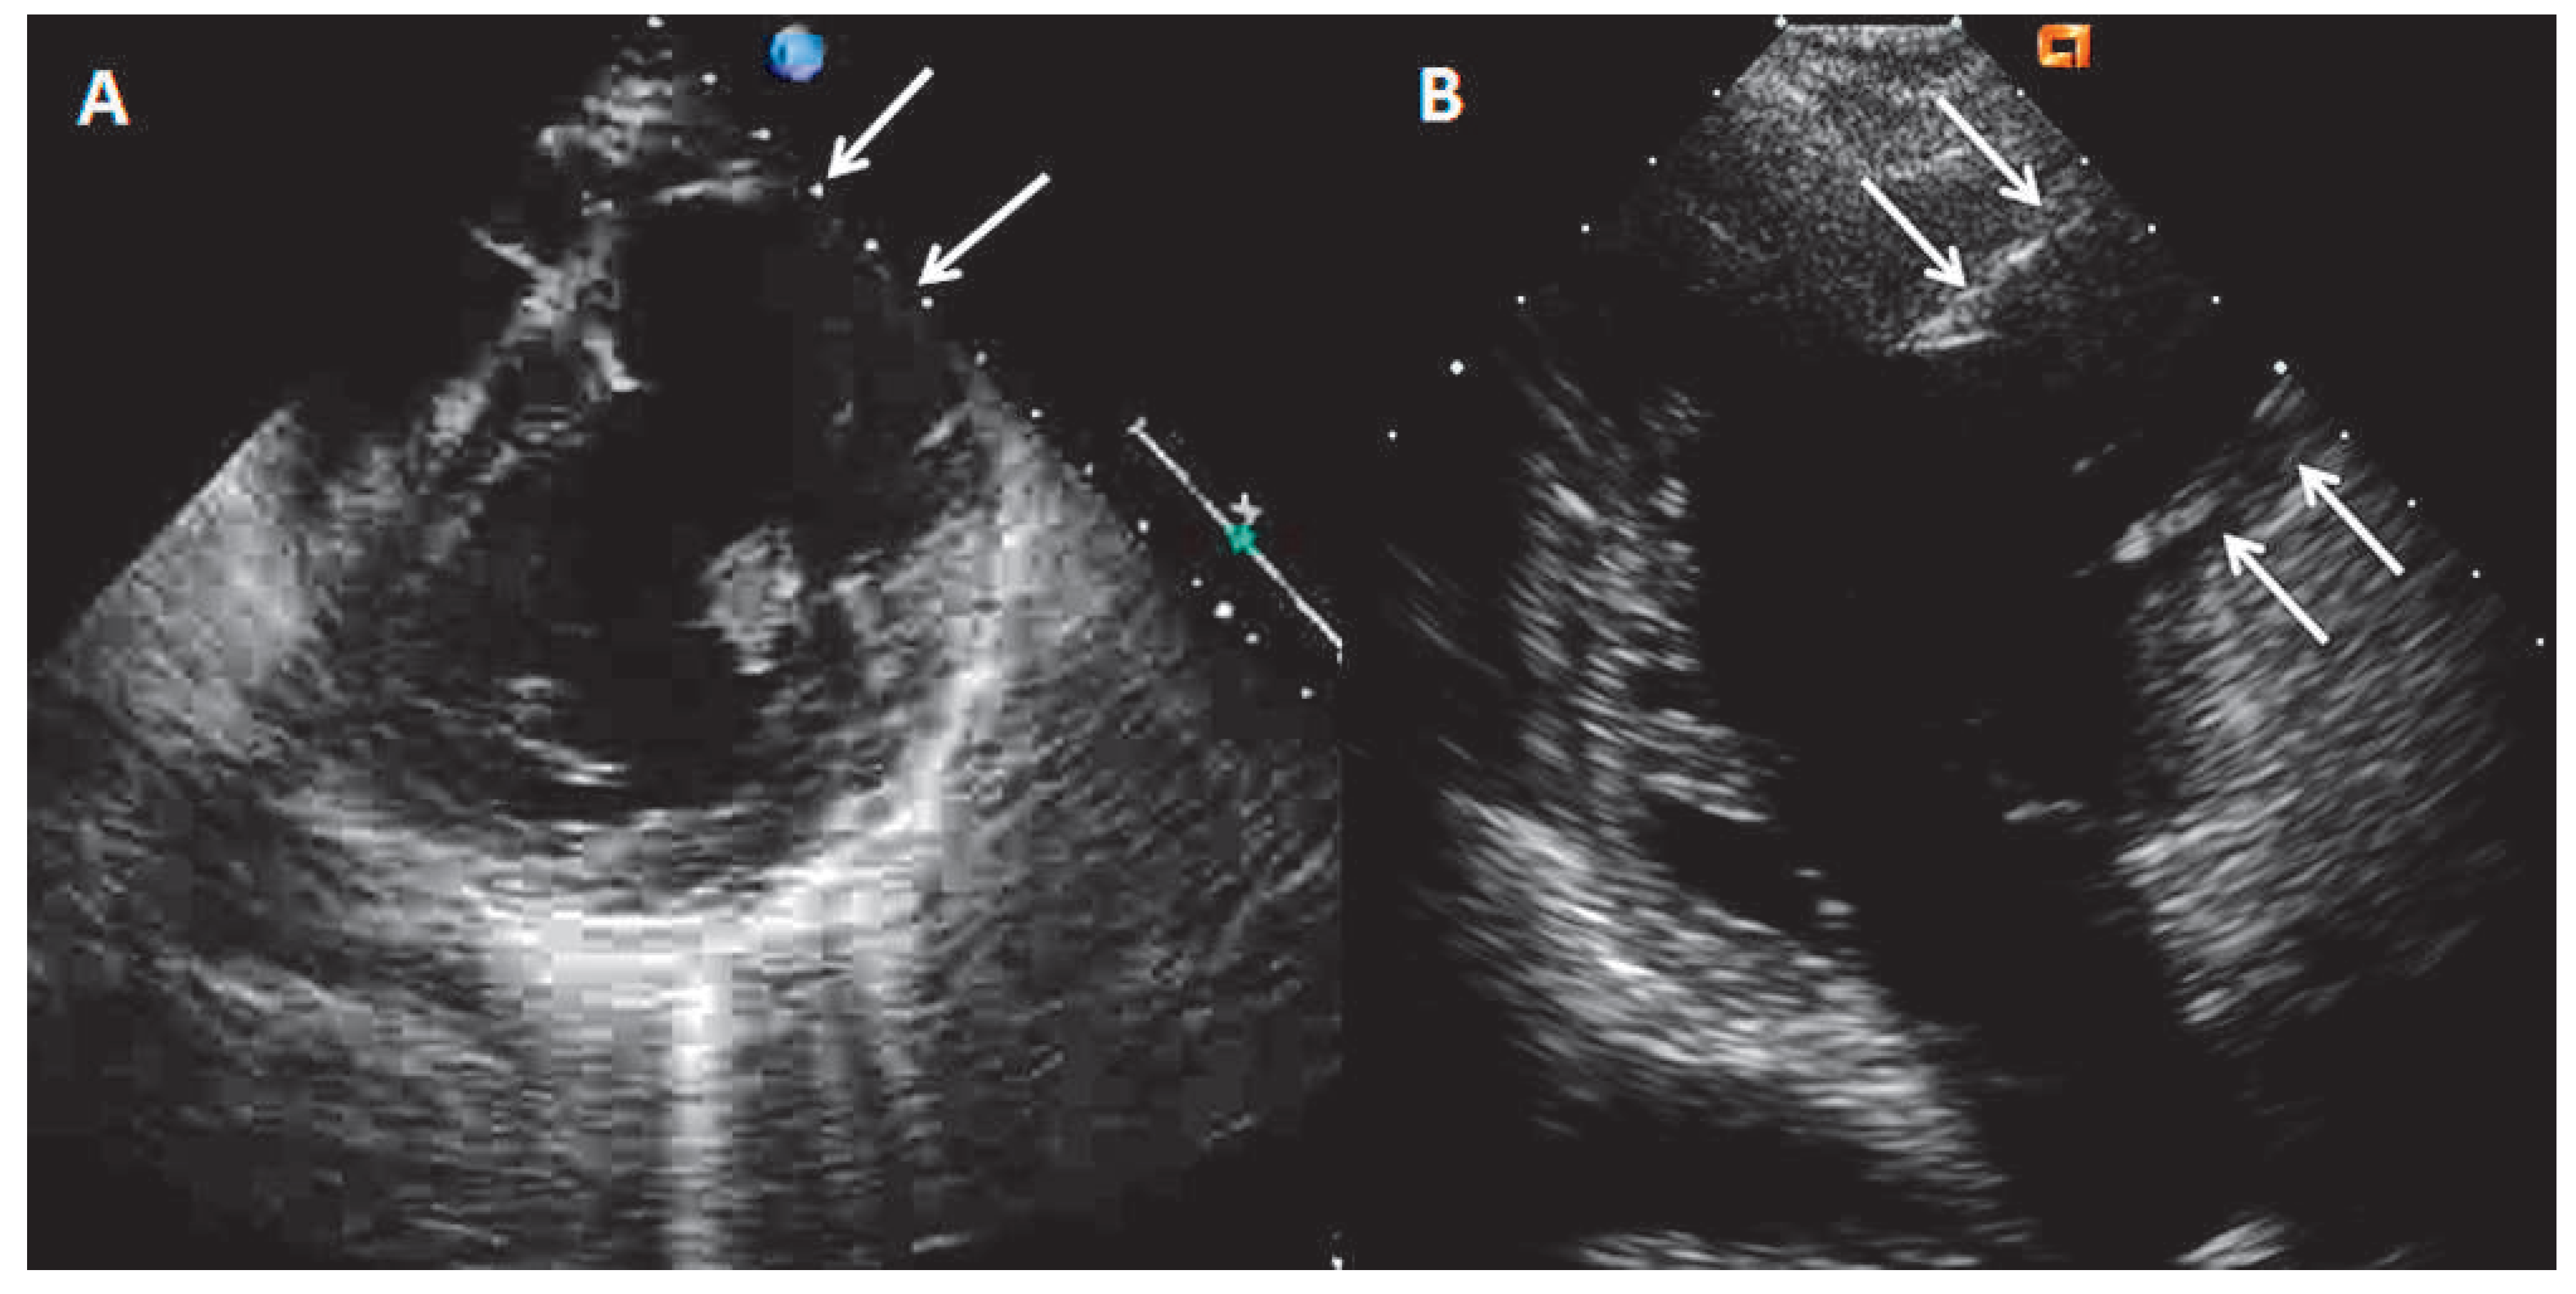

Magnetic resonance imaging (MRI) was performed to search for the possible explanations of the nature of the aneurysm. It showed transmural late gadolinium enhancement (LGE) of the entire akynetic aneurysmal wall, consistent with transmural scar (Figure 2A,B, arrows).

Figure 2. Cardiac MRI sagittal view showing the thinning of the wall of the aneurysm (A, arrow) and the presence of transmural late gadolinium enhancement (B, arrow).